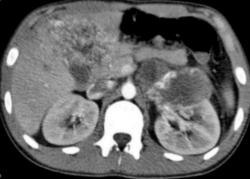

Метастазы. Наблюдение Владимира Борисовича Серова.

Метастазы. Наблюдение Владимира Борисовича Серова.

Множественные метастазы.

Множественные метастазы из не выясненного «первичного очага».

Молодой человек, 17 лет. Поступил в тяжелом состоянии, без сознания. Впервые недомогание почувствовал в сентябре, лечился в районе. До этого был здоров, закончил кадетское училище, поступил в училище летчиков гражданской авиации. На УЗИ лимфоаденопатия, кисты в печени. Периферических лимфоузлов не выявлено.